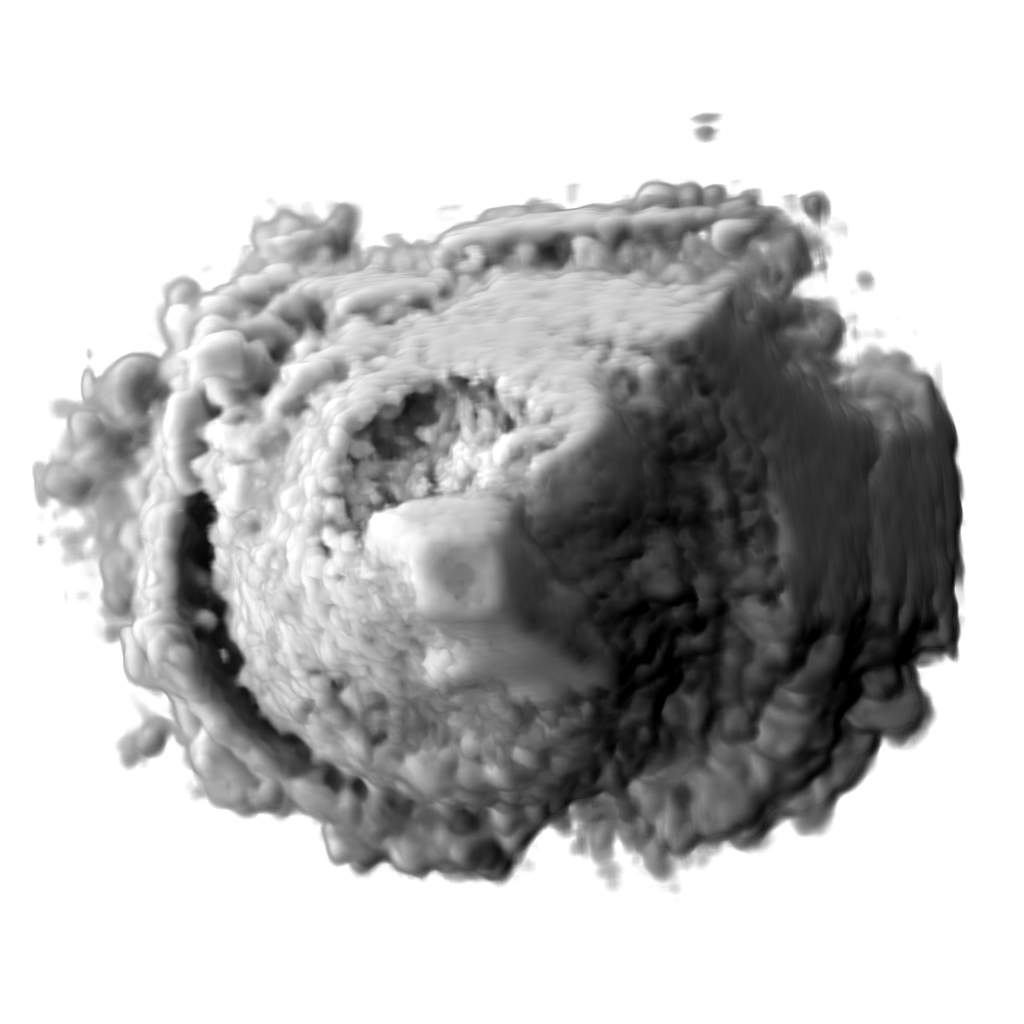

Recent works show that global illumination models based on gradient-free methods are suitable for rendering ultrasound volumes Ropinski10 ; solteszova10 . Ropinski et al. described a volumetric lighting model which simulates scattering and shadowing Ropinski10 . They use slice-based volume rendering from the view of the light source to calculate a light volume and raycasting to render the final image (see Figure 7b). A perceptual evaluation of the generated images indicates, that the proposed model yields stronger depth cues than gradient-based shading. Šoltészová et al. presented a single-pass method for simulation of light scattering in volumes solteszova10 . Light transport is approximated using a tilted cone-shaped function which leaves elliptic footprints in the opacity buffer during slice-based volume rendering. They use a slice-based renderer with an additional opacity buffer. This buffer is incrementally blurred with an elliptical kernel, and the algorithm generates a high-quality soft-shadowing effect (see Figure 7c). The light position and direction can be interactively modified. While these two techniques have been explicitly applied to 3D US data, the application of other volumetric illumination models potentially also improves the visual interpretation of 3D US data. Figure 8 shows a comparison of six different shading techniques as applied to a 3D US scan of a human heart. While the first row of Figure 8 shows examples for the already addressed shading techniques, the second row shows three alternative approaches. Figure 8d incorporates scattering of light in volume data, as proposed by Kniss et al. kniss02halfangle . Their slicing technique allows textured slices to be rendered from both light and viewing direction simultaneously. By sampling the incident light from multiple directions while updating the light’s attenuation map, they account for scattering effects in slice-based volume rendering. Figure 8e shows the application of the directional occlusion shading technique schott09directionalocclusion . This technique constrain the light source position to coincide with the view point. Finally, Figure 8f shows the application of a technique based on spherical harmonic lighting lindemann10materials .

Refer to caption

(a)

(b)

(c)

Figure 7: (a): Diastole of the aortic valve on a modern ultrasound workstation using color-coding based on depth. (b): Rendering of 3D ultrasound of human heart with shadowing from the work of Ropinski et al. Ropinski10 and (c) rendered using the technique presented in the work of Šoltészová et al. solteszova10 .

Figure 8: Comparison of six volume shading models as applied to a 3D US scan of a human heart.

Advanced illumination techniques are being now implemented in the commercial ultrasound workstations. Some workstations use additional color coding based on depth. Deeper tissues are colored with cold tones such as blue while close regions have red and orange tones. This effect has been firstly described by Einthoven Einthoven1885 and is also referred to as chromostereopsis Allen81 . Figure 7a shows a chromatic depth-encoding rendering of a 3D human heart in a modern ultrasound workstation.